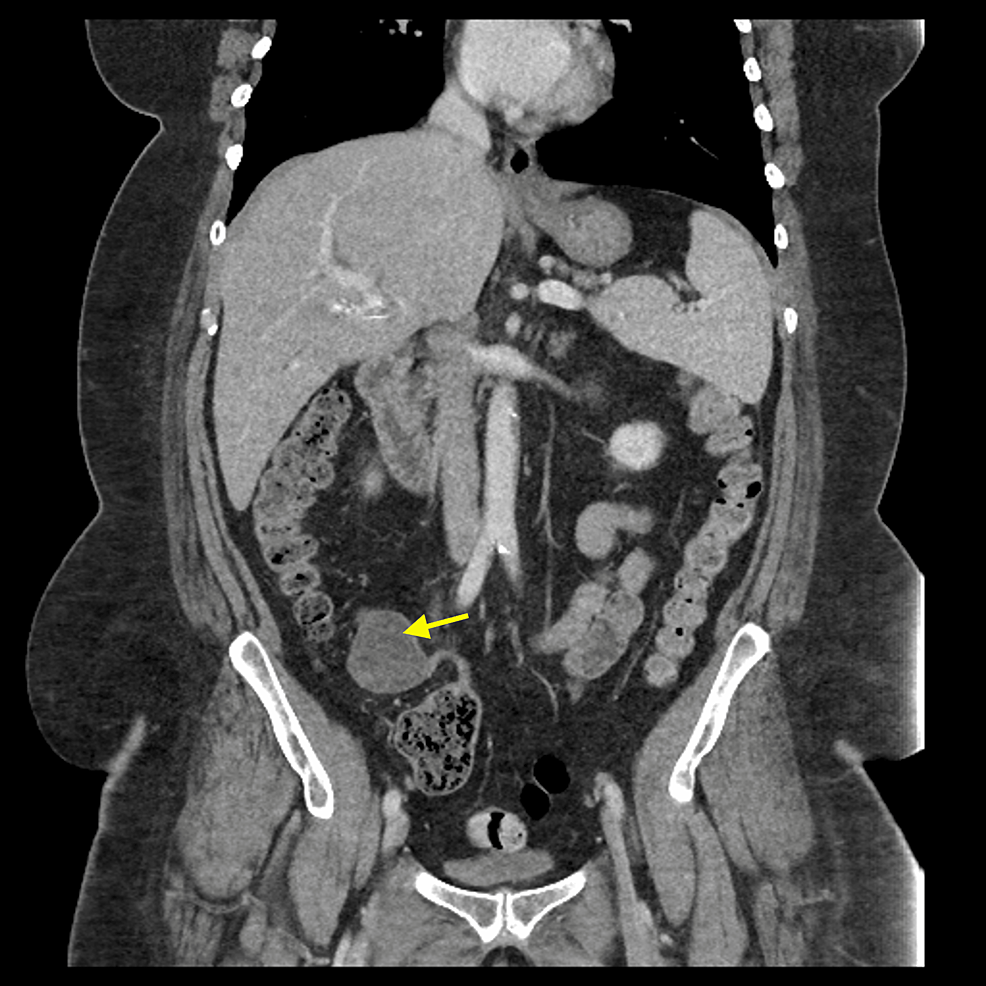

A 59-year-old male presented with microscopic hematuria. Renal ultrasound showed a large tubular lesion in the pelvis. CT abdomen and pelvis with IV and oral contrast demonstrated a 14.5 cm x 6.3 cm x 5.6 cm peripherally calcified tubular fluid attenuation lesion in the right hemipelvis. Though surgery was recommended for management, the patient declined surgery and wished to be managed non-operatively. The patient’s request was followed, and the patient was counseled that if the findings did not normalize on follow-up imaging after non-operative management, then surgery would be highly recommended. A follow-up CT scan with IV contrast five months later re-demonstrated the RLQ tubular cystic mass measuring 14.4 cm x 5.3 cm in the coronal plane with heterogeneous mural calcifications lying adjacent to the appendiceal tip. An open appendectomy was performed and the cystic appendiceal mass was removed (Figure 1). Because pathological examination demonstrated an LAMN confined to the appendix with an intact serosa and proximal and mesenteric bowel margins negative for neoplasms, staged as pTis, appendectomy alone was considered suitable for treatment.

To reduce risks of rupture and PMP progression and examine for the presence of LAMN pathologically, surgical removal of the appendix is crucial for further diagnosis and management [1-3]. Options for removal include open and laparoscopic resection. While open surgery is sometimes recommended to prevent LAMN rupture and PMP, there are documented cases of rupture and PMP in both open and laparoscopic resection with no comparative study available [5]. Including a cuff of the cecum without involving the ileocecal valve is preferred during appendectomy to ensure removal of the lesion [6]. Gross examination shows a cystically dilated mucinous appendix with a hyalinized, thin, fibrotic, or calcified wall and a smooth, corrugated, or granular lining (Figure 1) [1-2]. Because LAMN does not spread via the hematogenous or lymphatic route, an appendectomy is generally acceptable for the management of LAMN confined to the appendix on pathology, with conservative follow-up and surveillance if the appendectomy margins involve acellular mucin or neoplastic epithelium (Figure 5) [2, 7-8]. If acellular mucin is extruded on the appendiceal serosal surface without peritoneal dissemination, an appendectomy with close observation and evaluation for PMP via routine imaging appears to be sufficient [1-2]. Though recommendations on imaging frequency and duration may vary given there are no formal guidelines, we recommend annual CT imaging for five to ten years. Additionally, supplemental right hemicolectomy does not provide advantages over appendectomy in these patients and can involve the retroperitoneum, which may result in the seeding of the mucinous epithelium [2, 8]. If there is peritoneal dissemination, management may require appendectomy, irrigation, a biopsy of peritoneal nodules, peritonectomy, and chemotherapy [3].